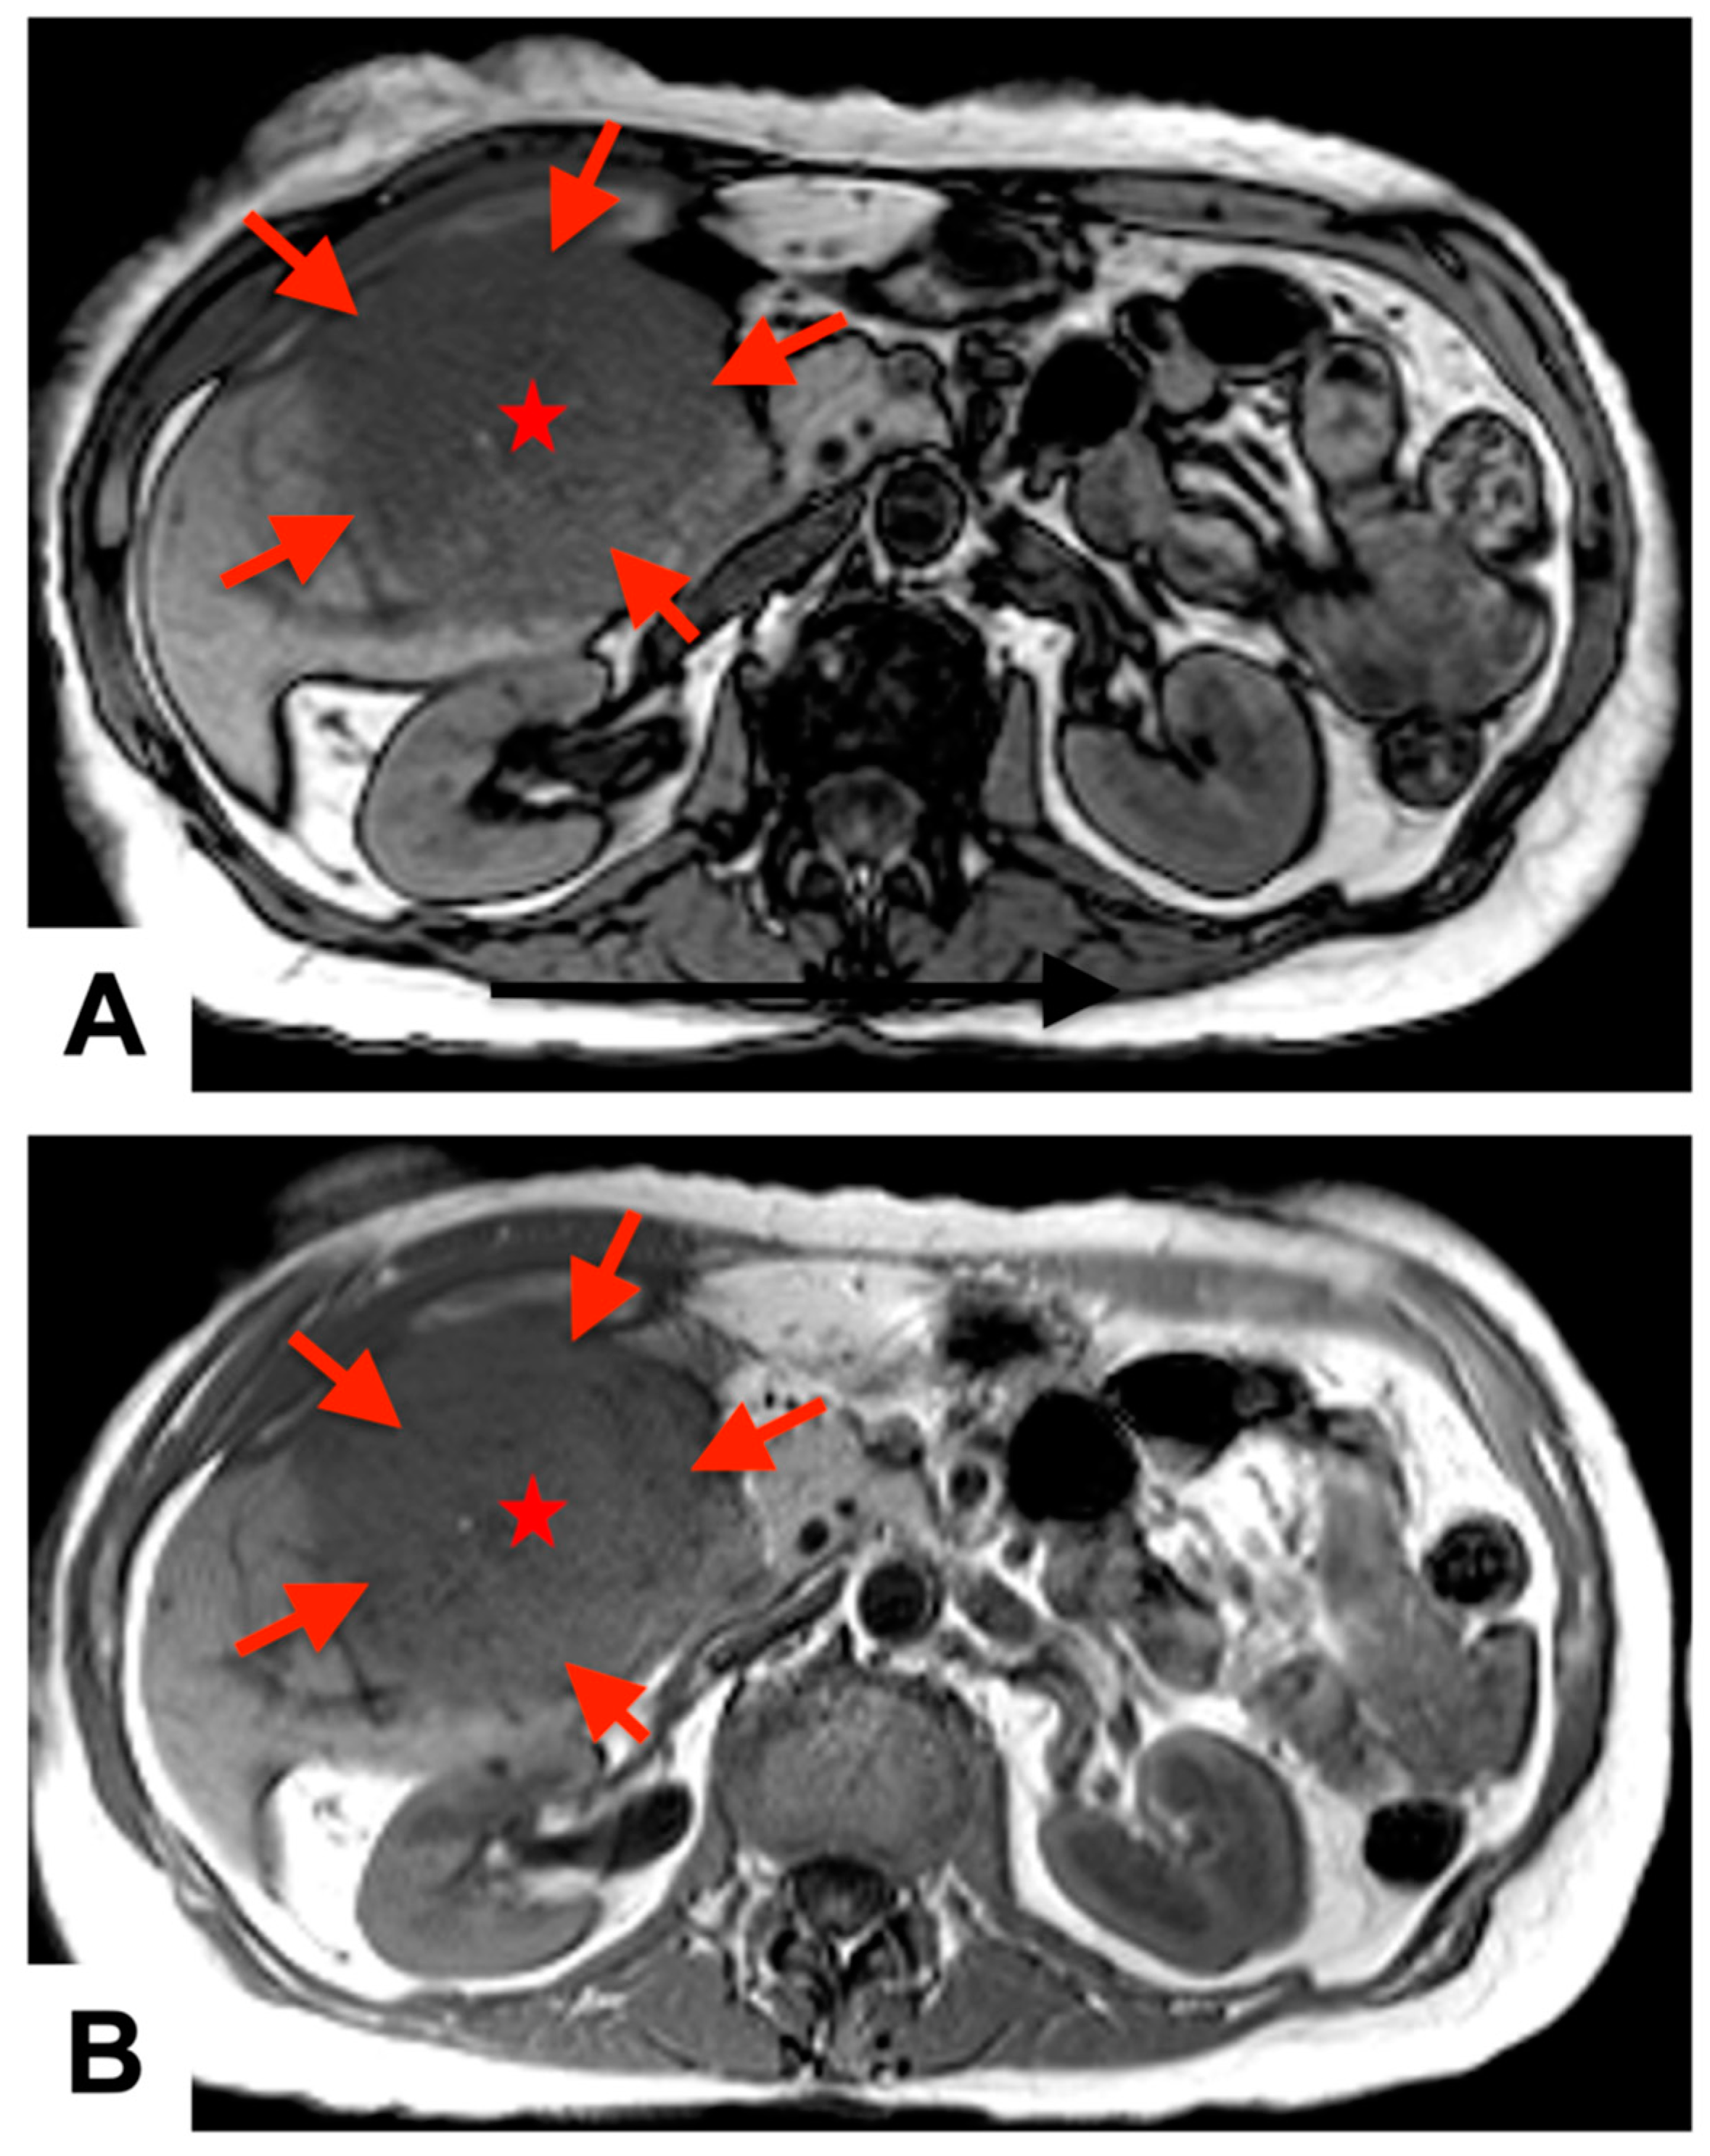

1.1. Case Report

Figure 1. Preoperative magnetic resonance imaging: T1 (A) and T2 (B) axial phase views demonstrate a large, heterogeneously enlarging, exophytic hepatic mass (red arrows and stars) in the posterior segment of the right lobe of the liver, measuring approximately 13.0 × 10.0 cm2 in size.